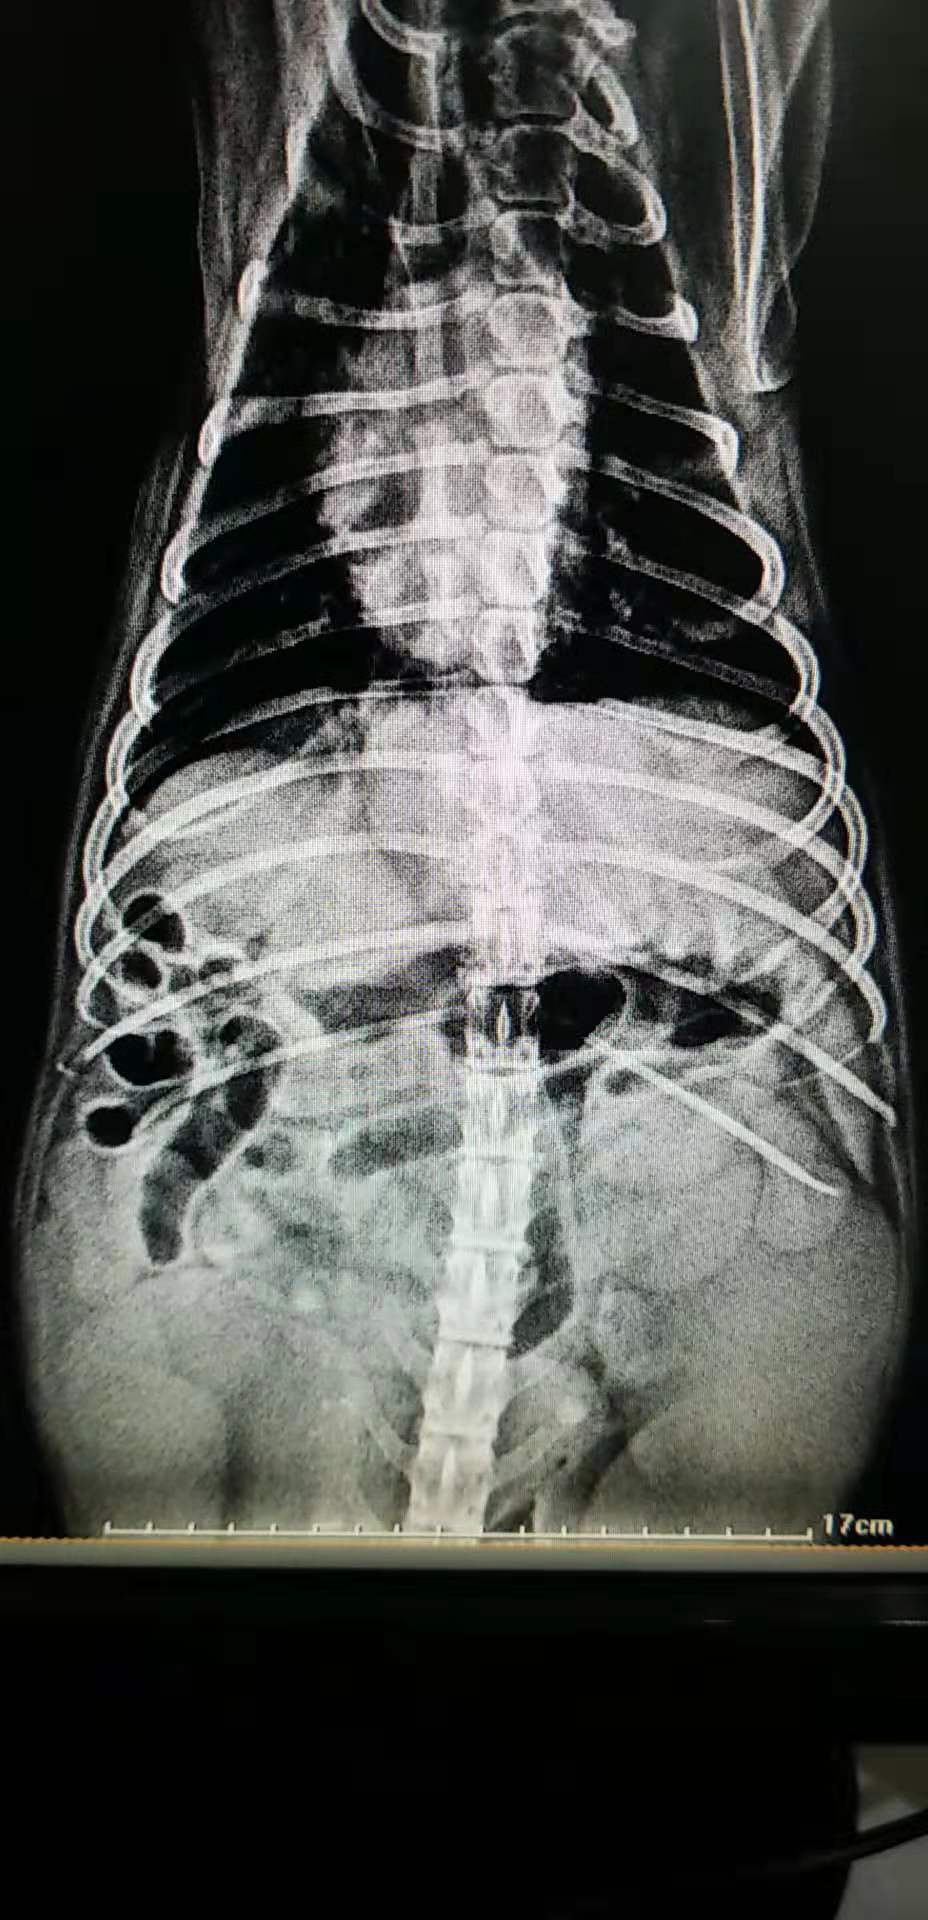

X光的摄片

- 实验室检查:血常规白细胞指标升高约4倍,生化球蛋白升高,x光可见腹腔子宫位置扩张占位。B超下腹腔多个液性暗区,最大子宫直径可达5cm。

- x光的检查:可见腹部子宫区有强回声占位。